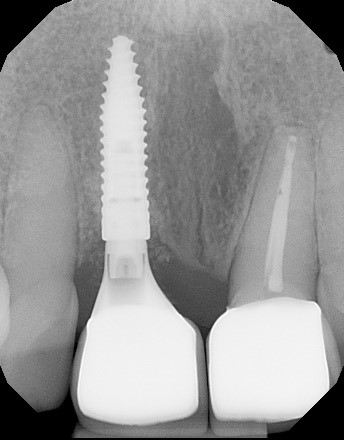

22/22 - Final radiograph one week post insertion.Immediate implant placement and regeneration of ridge using an allograft bone ring and Jason® membrane - Drs. Miller and Korn